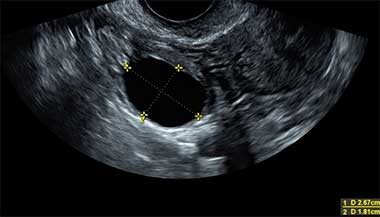

Quando você faz um ultrassom transvaginal e ele detecta múltiplos cistos na periferia dos ovários, isso não necessariamente é SOP! Esse diagnóstico acaba sendo um grande equívoco em diversos casos. O desbalanço hormonal que acontece na síndrome acaba provocando a formação desse padrão ovariano, mas muitas pacientes o têm de forma isolada, sem isso significar a presença da doença.